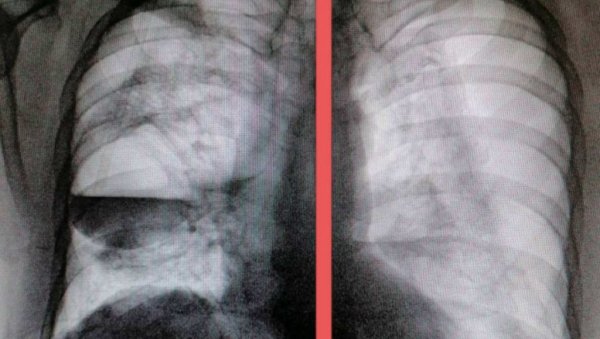

ДОКТОРКА Славица Плавшић, пулмолог у пензији, изазвала је велику пажњу на друштвеној мрежи "Твитер" пошто је на свом налогу поставила рендгенске слике плућа оболелог до корона вируса.

Фото:Твитер

Снимци плућа оболелих од ковид 19 пнеумоније нису реткост на друштвеним мрежама, али случај четрдесетогодишњака је изузетак по тежини болести и врло неуобичајеном радиолошком налазу.

- Надам се да ми нећете замерити. Снимци су узнемирујући. Трећи је нормалан снимак плућа. Прва два - обострани Пнеумоторакс, пуцање плућне марамице, гнојне шупљине у плућима, сепса, последица Ковид19. Мушкарац, 40 година. Већ три месеца се лечи у терцијарној установи. Сада је стабилан - била је њена објава на Твитеру уз приложене фотографије рендгенског снимка плућа.